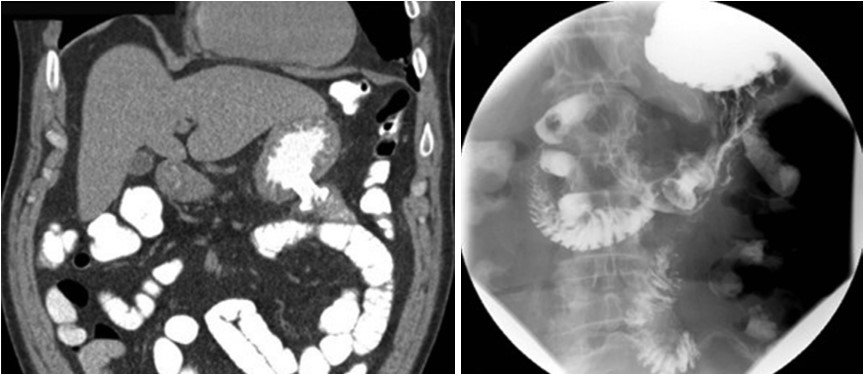

Endoscopic Ultrasonography (EUS)-guided anastomosis marks a significant milestone in the treatment of gastric outlet obstruction. This procedure enables the creation of a connection between the stomach and the jejunum, using a lumen-apposing metal stent (LAMS). The stent placement, which can be achieved directly or with balloon assistance under fluoroscopic and sonographic guidance, showcases the evolving precision in gastrointestinal interventions. Despite the limited experience, early data suggest promising outcomes, offering new hope to patients with this challenging condition.